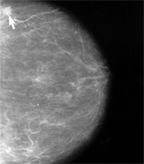

Standard mammography showing a small cancerous lesion (arrow); a new study found that adding tomosynthesis to digital mammography was more accurate than mammography alone

Breast tomosynthesis is a digital technique that produces two x-ray images of each breast. Multiple, low-dose images from different angles are produced for each breast and reconstructed, increasing sensitivity and specificity of the image. The radiation dose for the procedure is 3 mGy, the radiation exposure limit for a single mammogram, according to the US Food and Drug Administration (FDA). Unlike standard mammography where a two-dimensional image of the breast is used for diagnosis and can prevent views of specific areas, tomosynthesis (approved by the FDA in February of 2011) is a three-dimensional technique that can improve visualization.